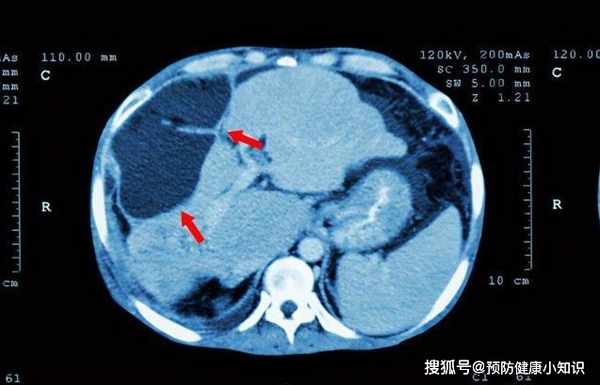

經過進一步的檢查之後,通過肝CT發現,王女士的肝臟上有一塊5公分左右的腫塊。基本可以確診為肝癌晚期了,需要及時手術治療。